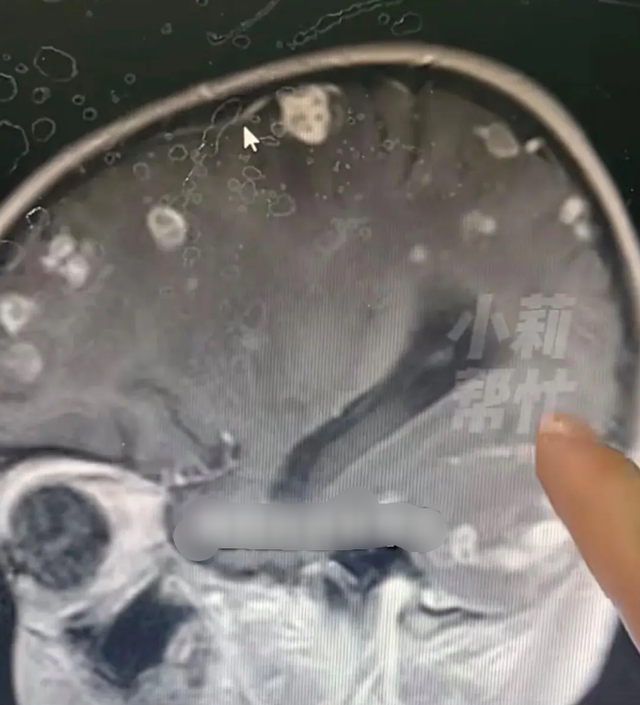

Theo Đài Phát thanh – Truyền hình Hà Nam, chương trình “Tiểu Lị Giúp Đỡ” đưa tin, mới đây tại Trịnh Châu (Hà Nam), một bé gái 6 tuổi bị sốt kéo dài suốt 17 ngày. Sau khi kiểm tra, bác sĩ phát hiện não của em xuất hiện hơn 20 ổ tổn thương, như thể bị “gặm nhấm”.

Phó trưởng khoa Hồi sức tích cực Nhi khoa, Bệnh viện trực thuộc số 1 Đại học Trịnh Châu – bác sĩ Hoắc Ngọc Phong cho biết, nguyên nhân là do nhiễm nấm Aspergillus fumigatus (nấm khói).

Thời điểm đó, bé theo gia đình về một căn nhà cũ đã bỏ trống lâu ngày để dọn dẹp. Trong thời gian ngắn, bé hít phải lượng lớn bụi mốc tích tụ trong nhà, khiến nấm xâm nhập vào máu và lan lên não.